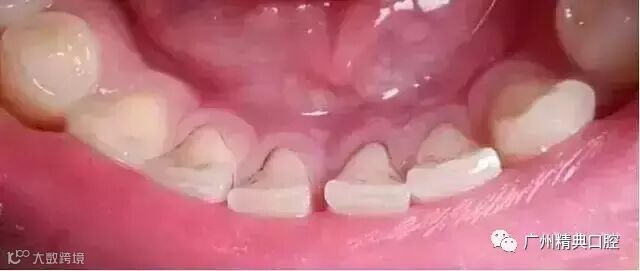

2牙齿出现了或深或浅的龋坏

牙齿出现龋坏,从外面看就表现为一个黑点,通常位于窝沟点隙(牙面上点状或线状凹陷)。龋齿的罪魁祸首是口腔中的某些细菌,但它们破坏牙齿也是需要时间的,从初期的变色到最终形成龋洞,通常需要1年半到两年。在此期间,我们多留心自己的牙齿,完全可能把龋坏扼杀在萌芽阶段。如何才能及时发现这种隐匿的蛀牙呢?找位好牙医,半年检查牙齿!

一旦确认牙齿上的小黑点是龋齿就应该尽早修补,以阻止病变的发展。如果任由其继续发展就会变成明显的龋洞,这时患者会对冷热酸甜等食物刺激敏感;当损伤进一步到达牙髓(即老百姓说的“牙神经”),就会疼痛难忍,严重影响日常生活。